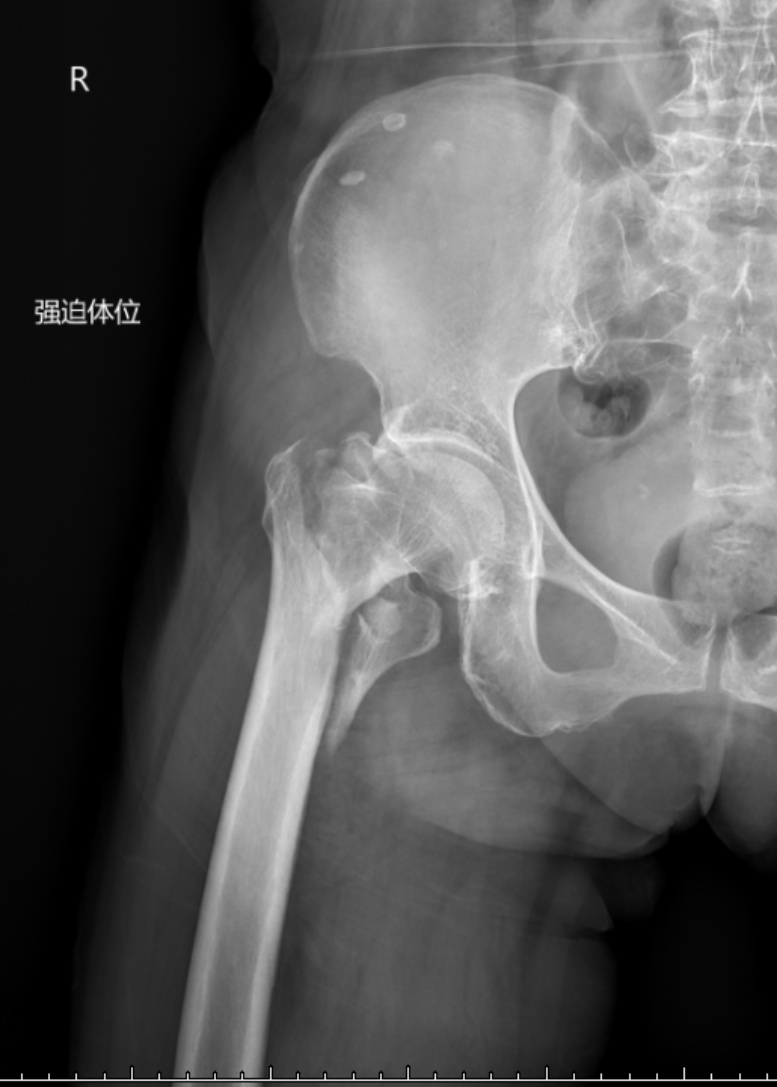

典型病例影像学表现见图1~10。图1为86岁女性右侧股骨转子间骨折(Evans Ⅲ型)患者,术前X线示骨折断端部分错位,术后X线示骨折位置可以及假体位置良好;图2显示了一名81岁男性患者,诊断为左侧股骨转子间骨折,类型为Evans V型,合并股骨干陈旧性骨折。患者接受了生物型加长柄半髋关节置换手术,并进行了股骨近端的钢丝捆扎内固定。术后X线示假体位置良好,股骨近端予钢丝捆扎固定;图3为87岁女性左侧股骨转子间骨折(Evans V型)患者,术后X线示假体位置良好,股骨大小转子骨折位置可,钢丝捆扎固定在位有效;图4为75岁女性左侧股骨转子间骨折(Evans V型)患者,术前X线示左侧股骨转子间骨折PFNA术后、骨折未愈合、内固定断裂。术后假体匹配良好,股骨近端钢丝内固定稳定可靠;图5为75岁男性左侧股骨转子间骨折(Evans IV型)患者,术后股骨大转子出现轻度位移,假体位置正常。图6为87岁男性左侧股骨转子间骨折(Evans V型)患者,给予DAA入路加长柄半髋关节置换,术前X线片,清晰地显示出左侧股骨转子间的骨折情况,术后X线影像,显示股骨的大小转子骨折位置良好,钢丝内固定装置在位稳定,假体位置良好;图7为77岁女性右侧股骨转子间骨折(Evans V型)患者,术前X线片显示右侧股骨转子间存在骨折且股骨大小转子均有累及和移位,术后X线片显示股骨小转子轻度移位,内固定装置位置稳定,假体位置良好;图8为70岁男性左侧股骨转子间骨折(Evans III型)患者,术前的X线片,清晰地显示了左侧股骨转子间的骨折情况,股骨近端髓腔钙化灶,术后假体位置满意;图9为77岁女性右侧股骨转子间骨折(Evans V型)患者,术前X线片,显示右侧股骨转子间及转子下部位骨折情况。术后假体匹配良好;图10为71岁男性右侧股骨颈骨折(Evans IV型)患者,术前X线片,显示右股骨转子间骨折的情况;术后X线表明股骨的大转子和小转子骨折位置保持良好,内固定装置稳固,术后假体位置正常。

(a) (b)

Figure 10. A 71-year-old male patient with right femoral neck fracture (Evans type IV). (a) Before surgery; (b) After surgery

10. 71岁男性右侧股骨颈骨折(Evans IV型)患者。(a) 术前;(b) 术后